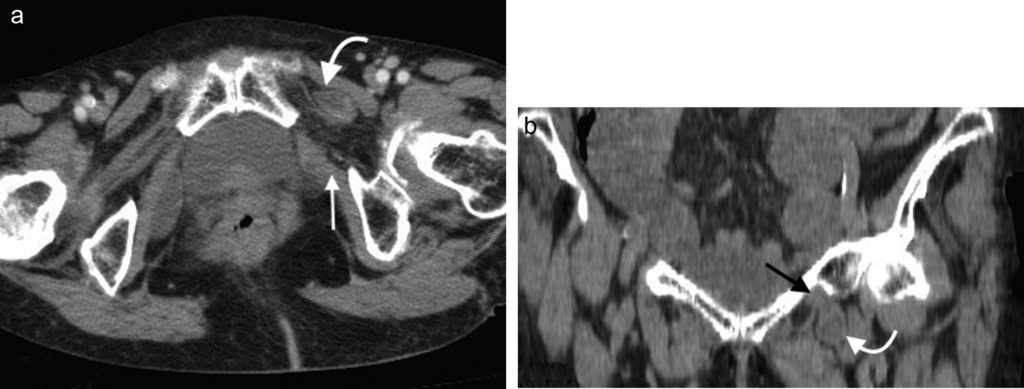

Hernia lumbar

Puede producirse por puntos d??biles en la pared abdominal posterolateral4. Estos son: el tri??ngulo lumbar superior o de Grynfelt, limitado hacia arriba por la duod??cima costilla, hacia adentro por el m??sculo cuadrado lumbar, lateralmente por el m??sculo oblicuo interno y hacia atr??s por el m??sculo espinal; y el tri??ngulo inferior o de Petit, confinado por el m??sculo oblicuo externo en sentido anterior, el m??sculo dorsal ancho en sentido posterior y la cresta il??aca en sentido inferior2,13.

En su mayor??a estas hernias son adquiridas (espont??neas, postraum??ticas o posoperatorias). Las espont??neas representan aproximadamente el 50% de todas las de la zona lumbar y con mayor frecuencia ocurren en el tri??ngulo superior, con un contenido que puede ser de asas intestinales, grasa retroperitoneal o el ri????n14.

Los s??ntomas suelen ser variables y confusos. Algunas veces la consulta se debe a un dolor lumbar o a una neuralgia posincisional1 (fig. 7).